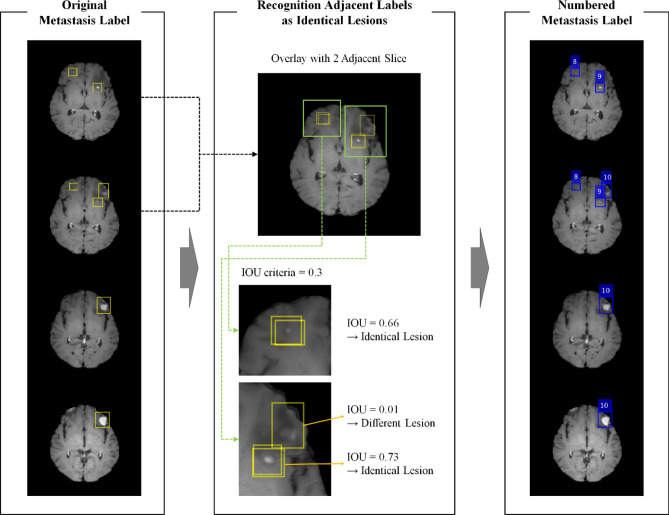

Existing object detection models provide predictions for each slice. However, clinically, the provision of predictions for each lesion is more practical. Thus, the DLA was designed to automatically derive the predictions for each lesion. For all labels on adjacent slices, the labels with an intersection > 0.3 intersection over union (IoU) were recognized as lesions, and each lesion was assigned an independent number (Fig. 5). As the DLA was designed for the detection of BM with a diameter > 5 mm that should be observed over two or more slices with a slice thickness of 3 mm, labels in a single slice were excluded for training and evaluation.

Figure 5.

The flowchart for recognition of adjacent labels as identical lesions. Each label was identified per lesion and granted the lesion number for each lesion. Yellow boxes show the original labels and blue boxes show the label that the lesion placed more than two adjacent slices. This figure was generated by MATLAB (MathWorks, R2020b, Natick, MA, USA) and PowerPoint 2016 (www.microsoft.com).